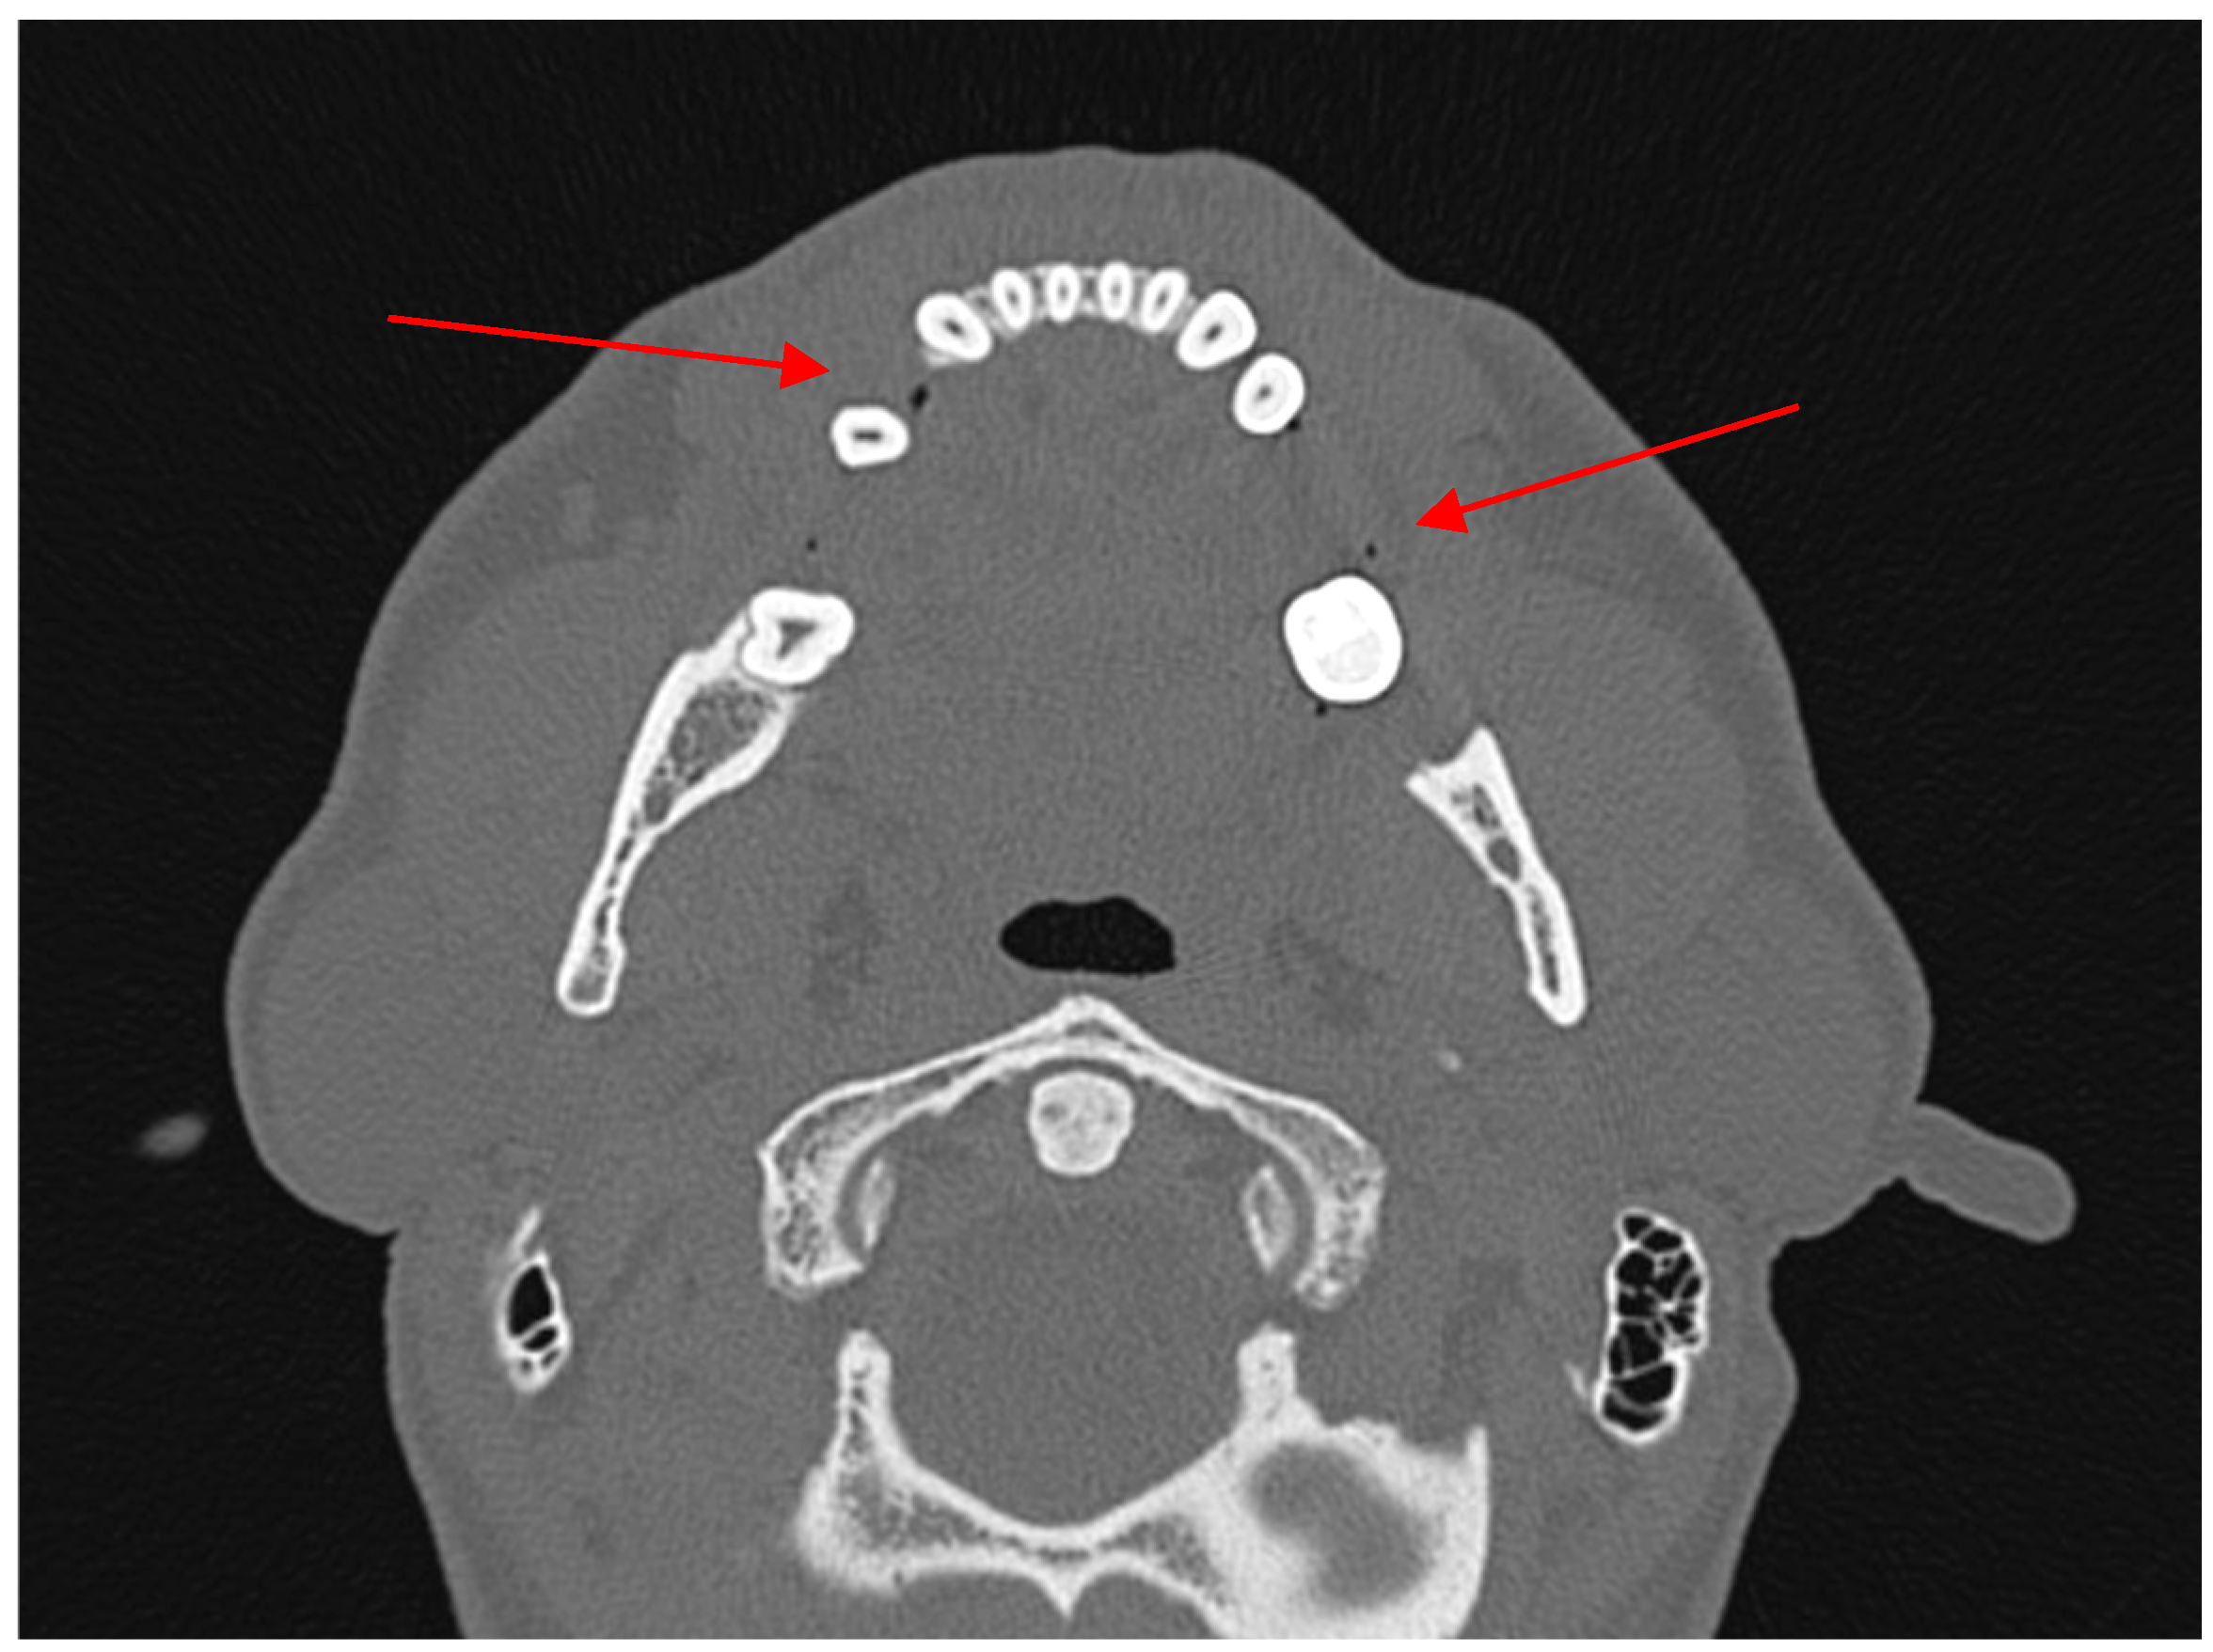

- True positive (TP)—diagnosed body/angle fracture + presence of AS in soft tissues.

- False positive (FP)—no body/angle fracture + presence of AS in soft tissues.